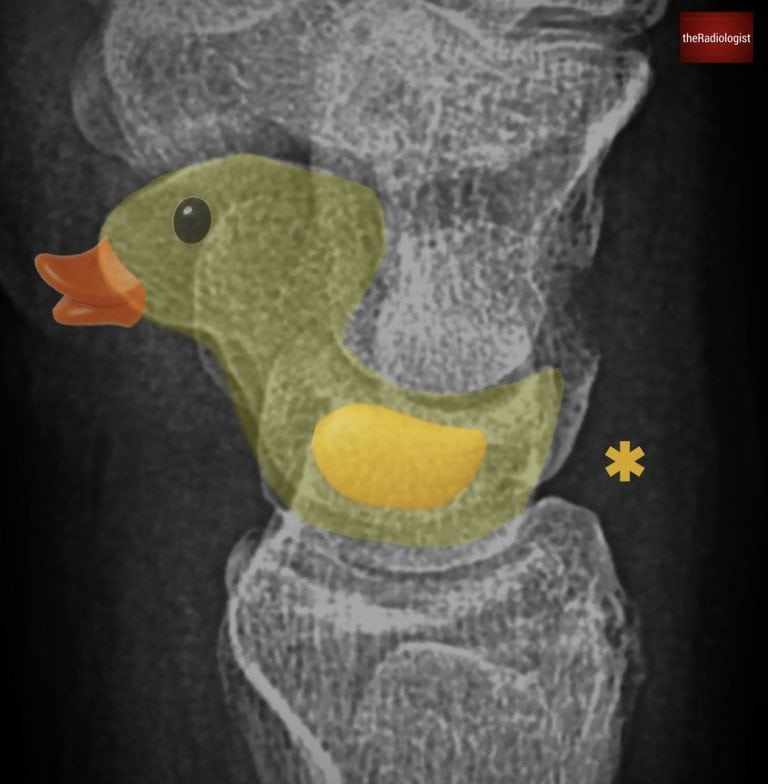

Next, review the dorsal aspect of the proximal carpal row for a triquetral fracture. This is the second most common carpal bone fracture after the scaphoid and is often seen after a fall onto an outstretched hand with hyperflexion. On the lateral film you’re looking for a small piece of bone dorsal to the proximal row – look for the pooping duck sign! The shape of the lunate and scaphoid can just about be made into a duck so you’re looking for a duck poo just behind this.

The shape of the scaphoid and lunate on a lateral view can look like a duck – look for a duck poo just behind this (star) which could represent a triquetral fracture.